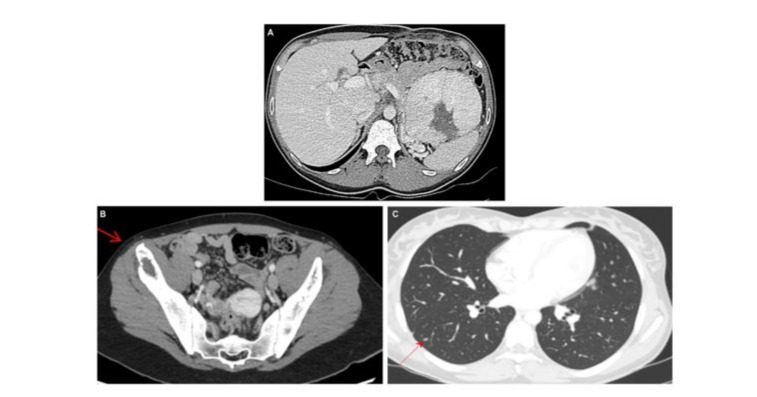

Seven months later, the patient received a first line of treatment with NIVOLUMAB/IPILILUMAB and had a favorable clinical and biological response. CT showed a stable disease according to RECIST 1.1 guideline (-24%) after 4 cycles of immunotherapy (Figure 3A-C). Treatment protocol was followed by NIVOLUMAB (480 mg every 4 weeks) as a maintenance therapy.

Figure 3: Evaluation after 4 cycles of treatment by NIVOLUMAB/IPILILUMAB. CT evidence shows a partial responding disease using the RECIST 1.1 guidelines (-24%), with stability of primary renal lesion measuring 10 cm (A), but reduction of lytic lesion of the right iliac wing (B) and reduction of since and numbers of multiple pulmonary nodules (C).